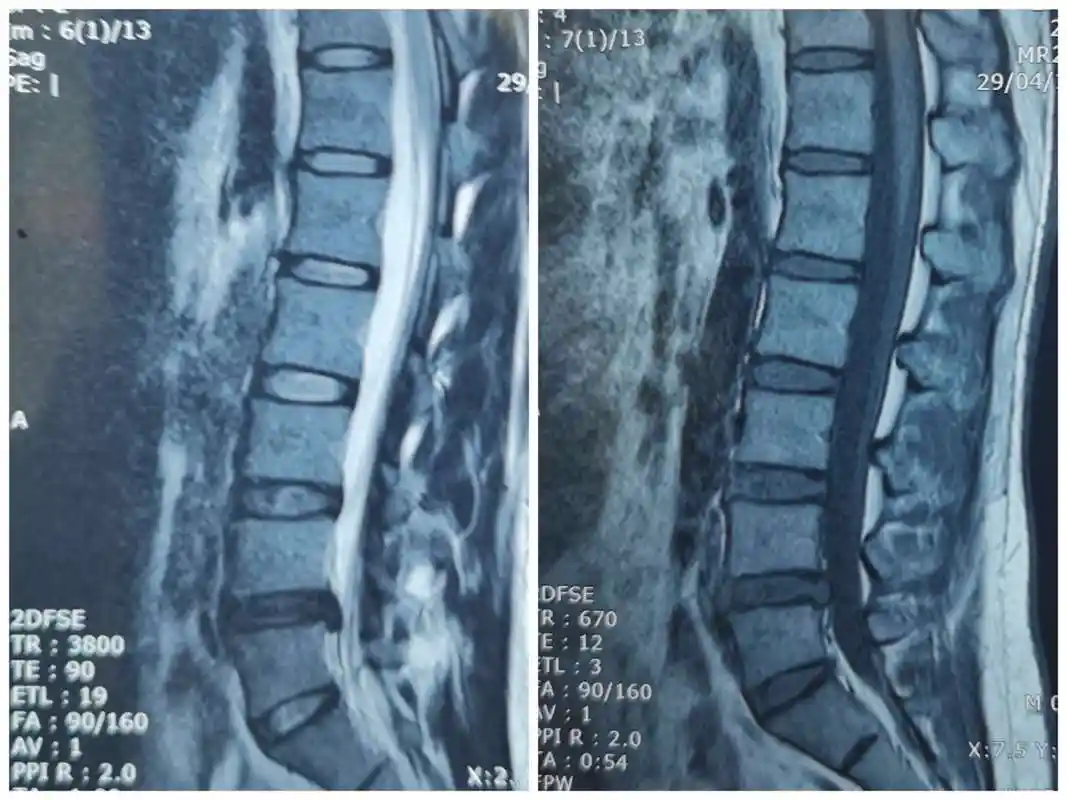

ct提示腰4/5椎间盘严重突出

请谈谈对这例腰间盘突出症病人治疗的看法

术前核磁术前腰5骶1间盘突出ct